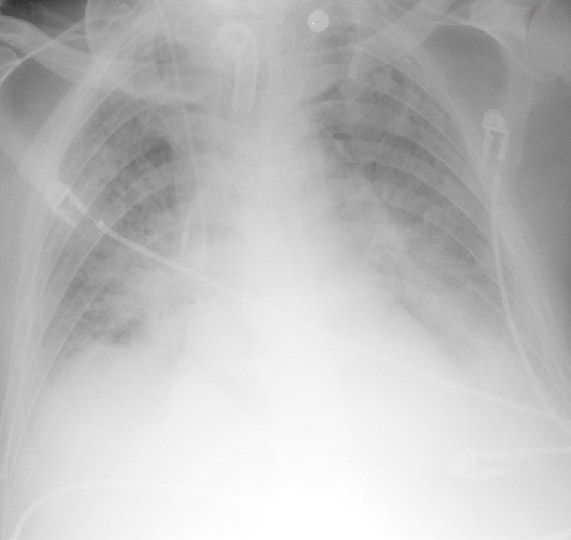

Pulmonary Edema and Symmetrical Bilateral Infiltrates Radiology Key Can Pulmonary Edema Be Seen On Xray Doctors may also order tests to confirm pulmonary edema or to rule out other conditions, including: Learn how to recognize the chest radiographic signs of hydrostatic and permeability pulmonary edema, and the factors that affect their appearance and resolution. Pulmonary edema is one of the most common entities encountered on routine chest imaging in both the inpatient and outpatient settings.. Can Pulmonary Edema Be Seen On Xray.

Clinical and Radiologic Features of Pulmonary Edema RadioGraphics Can Pulmonary Edema Be Seen On Xray Doctors may also order tests to confirm pulmonary edema or to rule out other conditions, including: Pulmonary edema is the abnormal buildup of fluid in your lungs that can cause shortness of breath and difficulty breathing. Pulmonary edema is one of the most common entities encountered on routine chest imaging in both the inpatient and outpatient settings. Learn about the. Can Pulmonary Edema Be Seen On Xray.